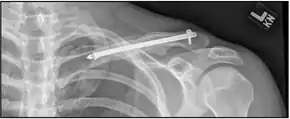

| X-ray of a left clavicle fracture | |

It is often caused by a fall onto a shoulder, outstretched arm, or direct trauma.[1][3] The fracture can also occur in a baby during childbirth.[1] The middle section of the clavicle is most often involved.[3] Diagnosis is typically based on symptoms and confirmed with X-rays.[2]

The basic method to check for a clavicle fracture is by an X-ray of the clavicle to determine the fracture type and extent of injury. In former times, X-rays were taken of both clavicle bones for comparison purposes. Due to the curved shape in a tilted plane X-rays are typically oriented with ~15° upwards facing tilt from the front. In more severe cases, a computerized tomography (CT) or magnetic resonance imaging (MRI) scan is taken. However, the standard method of diagnosis through ultrasound imaging performed in the emergency room may be equally accurate in children.[6]